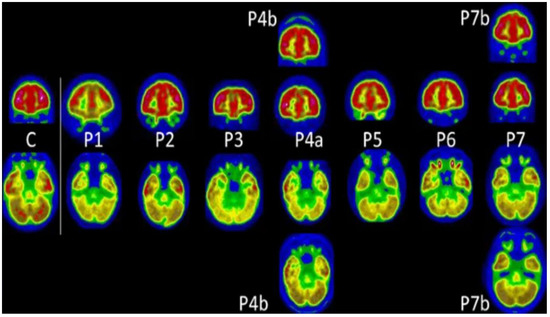

| Morand et al. [48] | Bilateral medial temporal lobes, brainstem and cerebellum, and also the right olfactory gyrus | Fatigue and cognitive impairment such as memory and concentration difficulties | Approximately 5 months | Retrospective/7 pediatric subjects (1 male and 6 females) |

- Morand, A.; Campion, J.-Y.; Lepine, A.; Bosdure, E.; Luciani, L.; Cammilleri, S.; Chabrol, B.; Guedj, E. Similar Patterns of [18F]-FDG Brain PET Hypometabolism in Paediatric and Adult Patients with Long COVID: A Paediatric Case Series. Eur. J. Nucl. Med. Mol. Imaging 2022, 49, 913–920. [Google Scholar] [CrossRef] [PubMed]